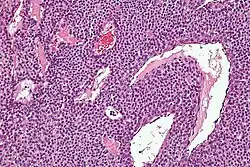

| Micrograph of a glomus tumor. H&E stain. | |

Histologically, glomus tumors are made up of an afferent arteriole, anastomotic vessel, and collecting venule. Glomus tumors are modified smooth muscle cells that control the thermoregulatory function of dermal glomus bodies. As stated above, these lesions should not be confused with paragangliomas, which were formerly also called glomus tumors in now-antiquated clinical usage. Paragangliomas do not arise from glomus cells, but glomus tumors do.

By histopathology, glomus tumors can be termed as follows:[8]

- Solid glomus tumor (75% of cases): Consisting predominantly of glomus cells, with poor vasculature and rare smooth muscle cells.

- Glomangioma (20% of cases): Tumors with a prominent vascular component.

- Glomangiomyoma (5% of cases): Tumors with prominent vascular and smooth muscle components.